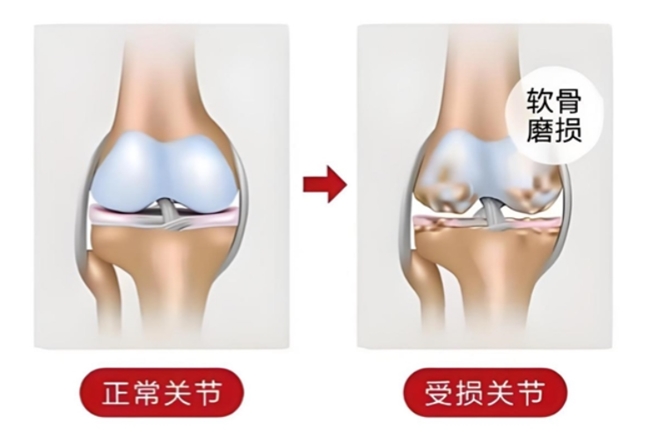

下楼梯时膝盖“咯吱”响、久坐后起身关节僵硬难动、阴雨天关节又肿又疼……这些反复出现的不适,可能是骨关节炎在“预警”。作为中老年人常见的关节疾病,骨关节炎会逐渐磨损关节软骨,若不及时干预,可能导致活动受限,影响日常生活。而针对骨关节炎的治疗,氨糖就是临床常用药物之一。那氨糖的作用和功效是什么?针对氨糖的两大类——硫酸氨基葡萄糖和盐酸氨基葡萄糖又该如何抉择呢?

硫酸氨基葡萄糖和盐酸氨基葡萄糖同属于氨糖产品,能够对出现磨损或受到侵蚀的关节软骨及其周围软组织起到修复作用;还能促进关节滑液生成并补充滑液,让关节软骨得到润滑,进而减少摩擦;此外,还可以对炎症反应进行抑制,防止关节病变持续加重[1]。

一项发表在世界顶级医学期刊《美国医学会杂志》(JAMA)上的研究显示,在治疗膝骨关节炎时,硫酸氨基葡萄糖缓解关节疼痛、改善关节功能的疗效优于盐酸氨基葡萄糖等33种骨关节炎常用治疗药物。该研究还指出,硫酸氨基葡萄糖能够延缓关节间隙变窄,从根源上改善关节结构,延缓关节磨损。而盐酸氨基葡萄糖在延缓关节间隙变窄这一作用上,目前效果还不明确[2]。